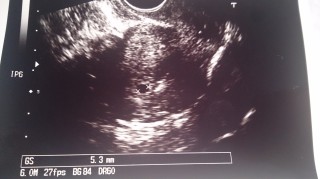

GS5.3㎜

不妊治療3年。

顕微授精で妊娠しました。

2回流産経験があり、

毎日喜びと不安でいっぱいです。

2週間後の検診が待ち遠しいです。